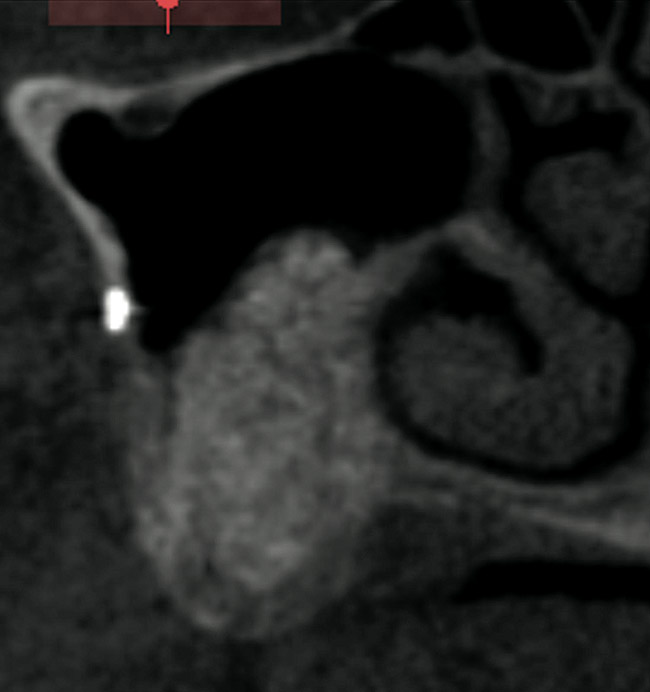

A 62-year-old woman was referred for fixed tooth replacement of the missing maxillary left cuspid, bicuspids, and first molar (Figure 11). Clinical and CBCT evaluation revealed an almost fully pneumatized maxillary left sinus along with alveolar width deficiency. The treatment plan called for a four-unit, implant-supported splinted fixed bridge. A left sinus augmentation along with a ridge split and interpositional bone graft consisting of rhBMP-2/ACS (INFUSE Bone Graft) and mineralized allograft (MinerOss) covered by a dense porous polyethylene mesh (Medpor®, Stryker, www.stryker.com) were done simultaneously (Figure 12, Figure 13 and Figure 14). Six months later, a follow-up CBCT revealed a well-incorporated graft with adequate bone volume and density for implant placement (Figure 15 and Figure 16). Final bridge fabrication followed 3 months later (Figure 17 and Figure 18).

Figure 15  Seven months post-graft CBCT.

Figure 15